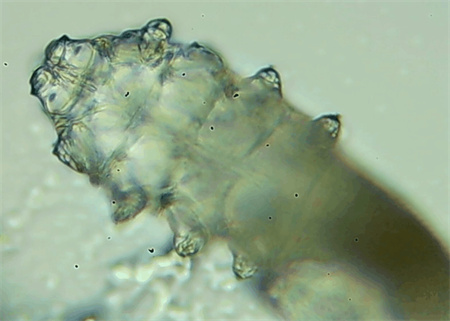

從一只眼睛的上眼瞼和下眼瞼處各拔3根睫毛,放在玻片上。

把玻片放到顯微鏡下觀察,通過電腦實時傳送的畫面,可以查看到這些拔下來的睫毛上是否有螨蟲。

結果,有6個人拔下來的睫毛上都發(fā)現(xiàn)了螨蟲。

這種螨蟲叫做蠕形螨,他們通常呈乳白色、半透明的細長狀,擁有四對腳。它們跟被子上的塵螨可不是同一種。

這些蠕形螨主要寄生在面部、頭皮、眼睛的睫毛毛囊、睫毛皮脂腺,以及瞼板腺里,以睫毛囊上皮細胞、腺體內(nèi)脂質(zhì)為食物。因此,即使經(jīng)常換洗床單、衣物,也可能會有蠕形螨。